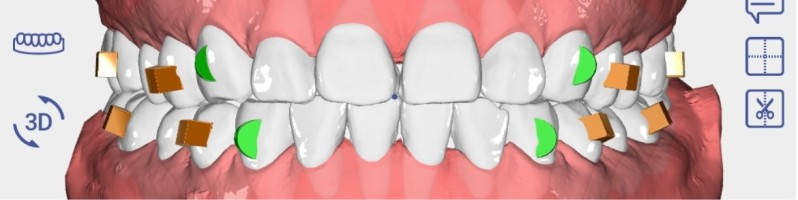

세라핀 투명교정 치료를 시작할 때는 먼저 구강스캐너를 이용하여 환자의 치아 데이터를 채득하게 됩니다.

기존의 인상재를 이용한 본뜨기 방식과 달리, 디지털 스캐너는 구역질이나 불편함 없이 정확한 3D 데이터를 얻을 수 있습니다.

이는 어린이 환자들에게 특히 유용한 방법으로, 인상 채득 과정에서의 거부감을 최소화할 수 있습니다.

채득된 디지털 데이터를 바탕으로, 앞으로 이루어질 치아 이동을 단계별로 예측하여 시뮬레이션합니다.

이 과정에서 치료 시작부터 완료까지의 전 과정을 3D로 미리 확인할 수 있어, 치료 계획을 보다 명확하게 수립할 수 있습니다.

최종적으로 이러한 디지털 설계를 바탕으로 세라핀 투명교정 장치를 정밀하게 제작하게 됩니다.

각 단계별 장치는 환자의 치아 상태에 정확히 맞춰 제작되어, 효율적인 치아 이동을 유도할 수 있습니다.